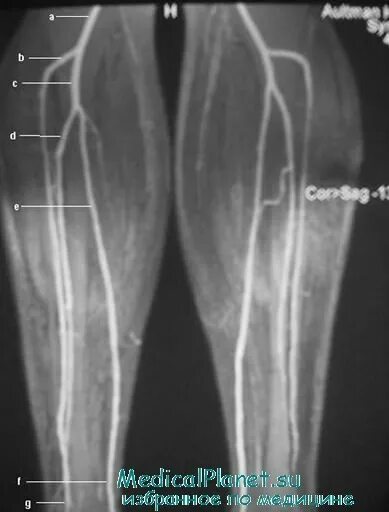

Артериография нижних конечностей. мскт флебография вен нижних конечностей. ангиография. ангиография сосудов нижних конечностей.

Мскт флебография вен нижних конечностей. магнитно-резонансная ангиография сосудов нижних конечностей. мра (магнитно-резонансная ангиография). кт флебография вен нижних конечностей.

Кт флебография нижних конечностей. магнитно-резонансная ангиография сосудов нижних конечностей. мрт флебография нижних конечностей. кт венография нижних конечностей.